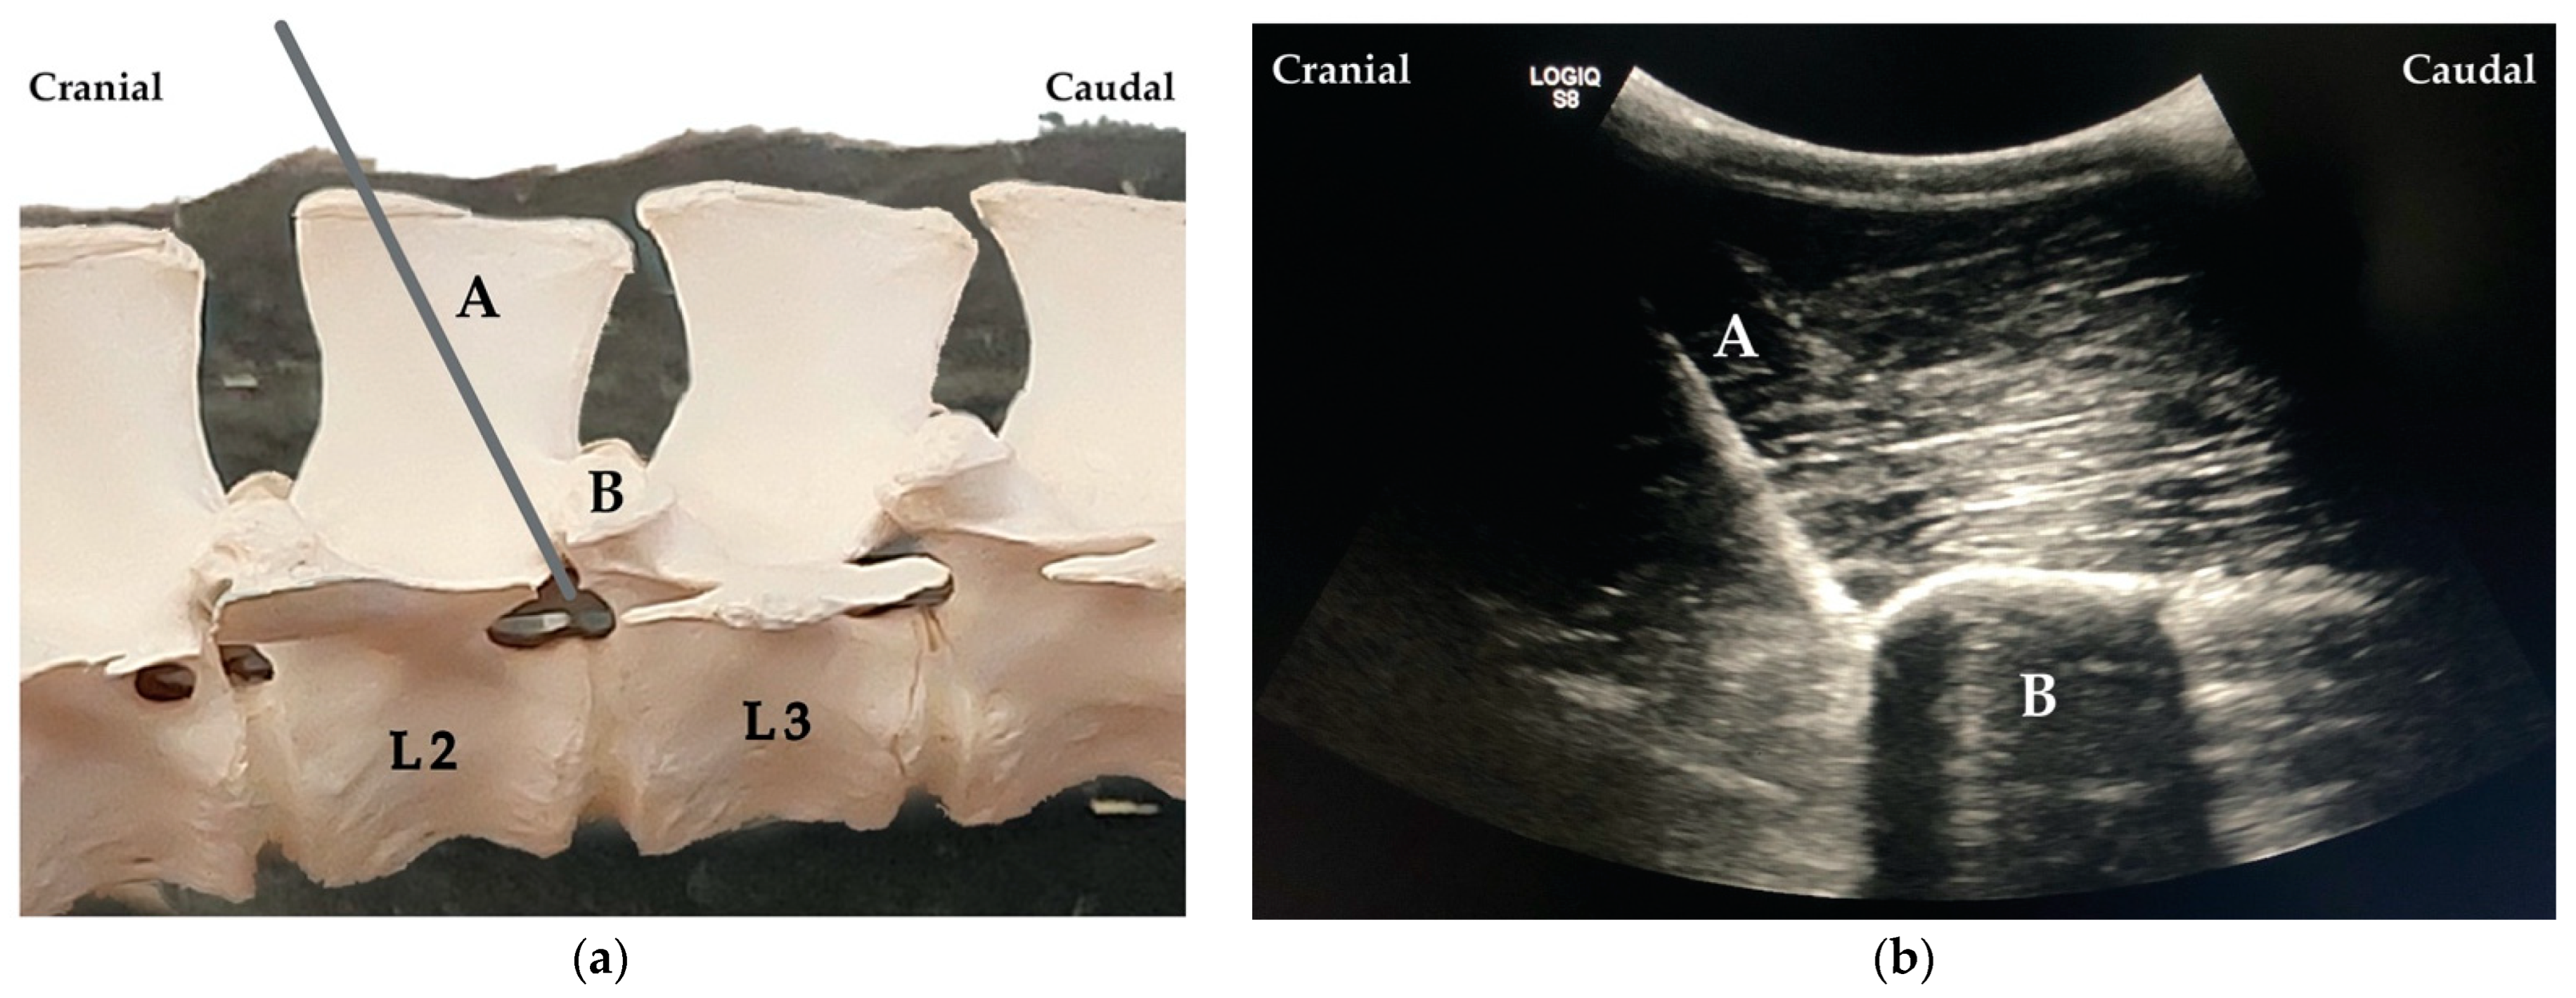

2.3.1. Ultrasound-Guided Technique: ESPB